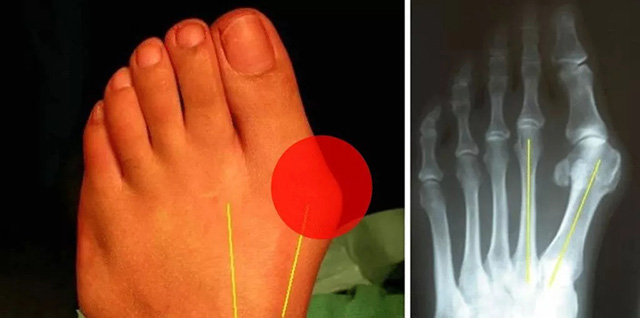

小朋友的足弓一般是三岁左右开始出现的,如果足弓发育不好受力线的影响会影响小朋友的走路姿势及平衡,甚至会导致拇外翻。拇外翻如下图:

我们走路一般都有一个足偏角,如上图所示,中间为正常,两侧为异常。如果不加以纠正,很可能会导致走路姿势异常。